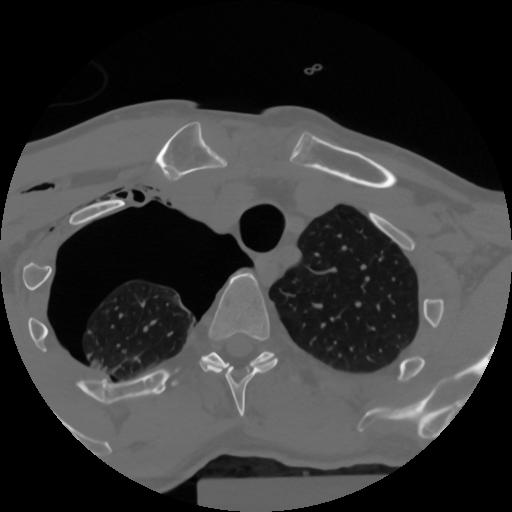

12 P.BLANDAS,,Vol,0.5,P.BLANDAS,,